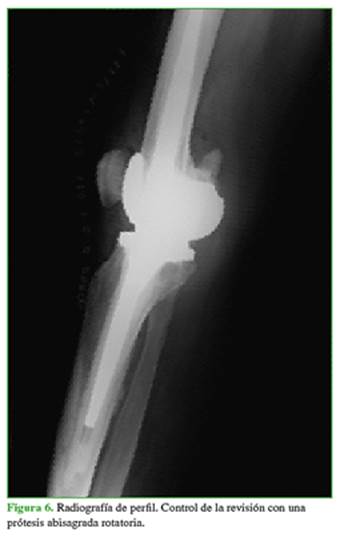

Durante la cirugía, se detectó la rotura del poste central del inserto de polietileno (liner) (Figura 5). Se procedió a retirar la prótesis primaria para luego implantar una prótesis abisagrada con plataforma rotatoria (Endo-Model NR®, Waldemar Link GmbH & Co. KG, Hamburgo, Alemania), con buena evolución hasta la fecha (15 meses después de la cirugía) (Figuras 6 y 7).